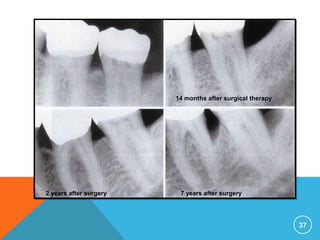

…RADIOGRAPHIC EVALUATION

 Radiographic examination must be individualized,

depending on the initial severity of the case and the

findings at the recall visit .

 These are compared with findings on previous

radiographs to check the bone height and look for

repair of osseous defects, signs of trauma from

occlusion, periapical pathologic changes, and caries.

14 months after surgical therapy

7 years after surgery2 years after surgery